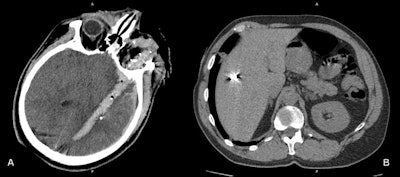

"We face all types of combat injuries. If the patient is stable enough and doesn't need urgent surgery, then CT is the modality of choice, and we scan from the top of the head to the sit (or sitting) bones. For the head, extremities, and sometimes the lungs, we often perform noncontrast CT, unless we suspect vascular injuries. For whole-body CT, we use contrast enhancement," Makarenkov said.